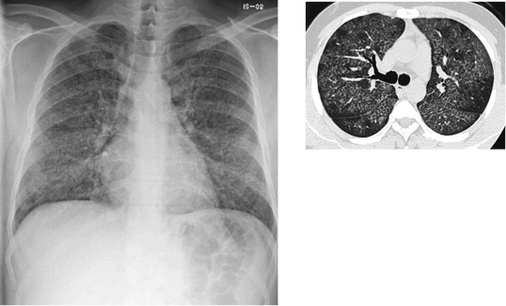

In der Thoraxaufnahme kommen im Gegensatz zu den klassischen Verlaufsformen mit nodulärem bzw. nodulär-retikulärem Bildmuster Milchglastrübungen zur Darstellung. Der Befund kann aufgrund der oft symmetrischen und bevorzugt perihilären Ausbreitung einem Lungenödem ähneln. Computertomographisch zeigen sich fokale Milchglastrübungen und Verdickungen der interlobulären Septen sowie des axialen Interstitiums, vereinbar mit einem Crazy-paving-Muster („crazy paving“ = Mosaikpflaster). Diese Befunde erinnern bildmorphologisch an eine primäre Alveolarproteinose (  Abb. 2 ). Im Gegensatz zur Alveolarproteinose finden sich jedoch zusätzlich unscharf begrenzte zentrilobuläre Verdichtungen und größere konfluierende Konsolidierungen (Alper et al. 2008; Doganay et al. 2010; Marchiori et al. 2007; Taeger 2011). Punktförmige Verkalkungen innerhalb der Konsolidierungen wurden von Marchiori et al. (2007) in 83 % der Fälle gesehen und als charakteristisch für eine Silikoproteinose beschrieben. Die Läsionen sind überwiegend dorsal angeordnet. In etwa 50 % der Fälle finden sich vergrößerte mediastinale Lymphknoten, die zum Teil auch verkalken (Marchiori et al. 2007), eierschalenartige Verkalkungen wurden jedoch nicht nachgewiesen. Uehlinger beschreibt erstmals 1949 bei starker Ausprägung der Erkrankung eine Betonung der Befunde in den Unterfeldern, diese wird auch in späteren Arbeiten bestätigt.